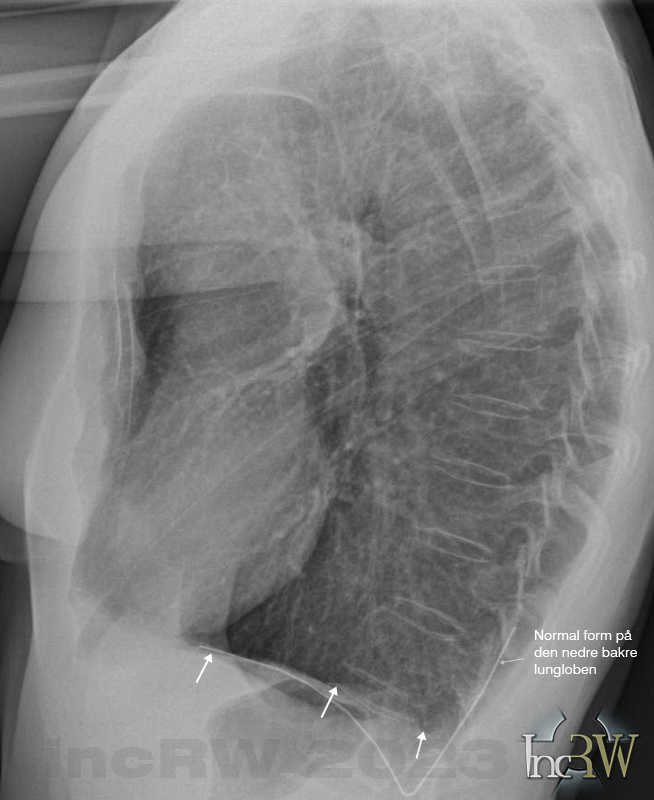

Diafragmans form kan vara olika hos olika individer utan att detta innebär att något är fel. Långa och smala personer har ofta mer utmärkande diafragmavalv med långt bakåtgående lungspetsar (lung-/pleurasinus) än hos överviktiga eller korta personer som får en mer utplanad valv/båge men som trotts detta utgörs av helt friska lungor.

Det finns sjukliga tillstånd som kan ge en mer avplanad diafragma eller en minskning av lungspetsen (pleurasinus) på röntgenbilden. Det kan vara vätska i lungsäcken (pleurit), pleuraadherenser1Lungsäcken nere i lungsinus kan växa ihop (pleuraadherens) efter tex. lunginflammation som då kan ses som plan diafragma på den drabbade sidan. Pleuraadherenser brukar dock ge typiska symtom i form av smärta vid andningsrörelser, långvarig hosta, viss andfåddhet, då de båda plaurabladen inte glider fritt mot varandra vid andning. Adherens i lungsinus kan även vara helt symtomfri. , vätska i buken (ascites), meteroism2Uppdriven buk som kan bero på mycket gaser i tarmarna., stor lever eller mjälte eller båda (hepatosplenomegali), fel på nervus phrenicus3Nerv som drar samman diafragmamusklerna vid inandning., lungemboli, subfreniska abscess4Varansamling i bukhålan under diafragman., stor tumör i buken, emfysem samt KOL5Kronisk obstruktiv lungsjukdom som kan innebära andningsbesvär med hosta och ökad slembildning i luftvägarna.. KOL kan även drabba icke rökande personer pga. passiv rökning, exponering av gaser/irriterande ämnen (i arbetet, etc.) och tidigare lunginflammation, mm. Vid uttalad emfysem kan man ibland även se att bröstkorgen tar en ”tunnliknande form”, som kan ses på sidobilden, med en ökad mängd luftförande vävnad bakom bröstbenet samt ofta med ett litet hjärta.